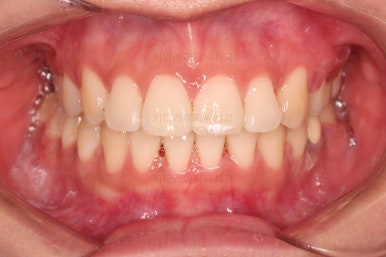

틈이 다 없어졌고, 교합도 양호합니다.

무엇보다 임플란트 없이 결손부위가 깔끔하게 채워졌고요.

매우 다행으로 사랑니도 다 있었기 때문에 마치 큰 어금니가 다 있는 것과 같은 상황이 되었습니다.

전후 비교 해볼게요.

입안의 모습은 더할나위 없이 잘 개선되었고요.

상하좌우 이 뽑은 위치와 크기가 달라 이정도 중앙선은 매우 잘 맞는 상황인거고요.